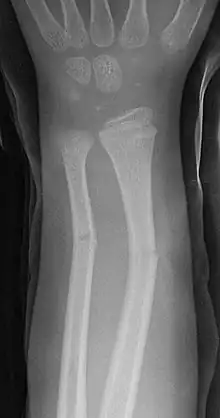

| Greenstick fractures on X-ray. | |

A greenstick fracture is a partial bone break that typically occurs in children due to their more flexible and resilient bone composition. This fracture pattern is characterized by a break on one side of the bone while the other side remains intact and bends, similar to breaking a young, green tree branch. Greenstick fractures most commonly affect the long bones of the forearm (radius and ulna) but can also occur in other long bones throughout the body. Treatment generally involves immobilization with a cast to allow proper bone healing, though in some cases, it may be necessary to realign the bone before casting.

On the side of the fracture that underwent tension, imaging may show bone cortex disruption. On the side that underwent compression, cortex may bulge outward, similar to a torus fracture.[1]

Greenstick fractures are usually identified with ease on X-ray of the affected limb, showing a long bone fracture that does not cut all the way through.[2]